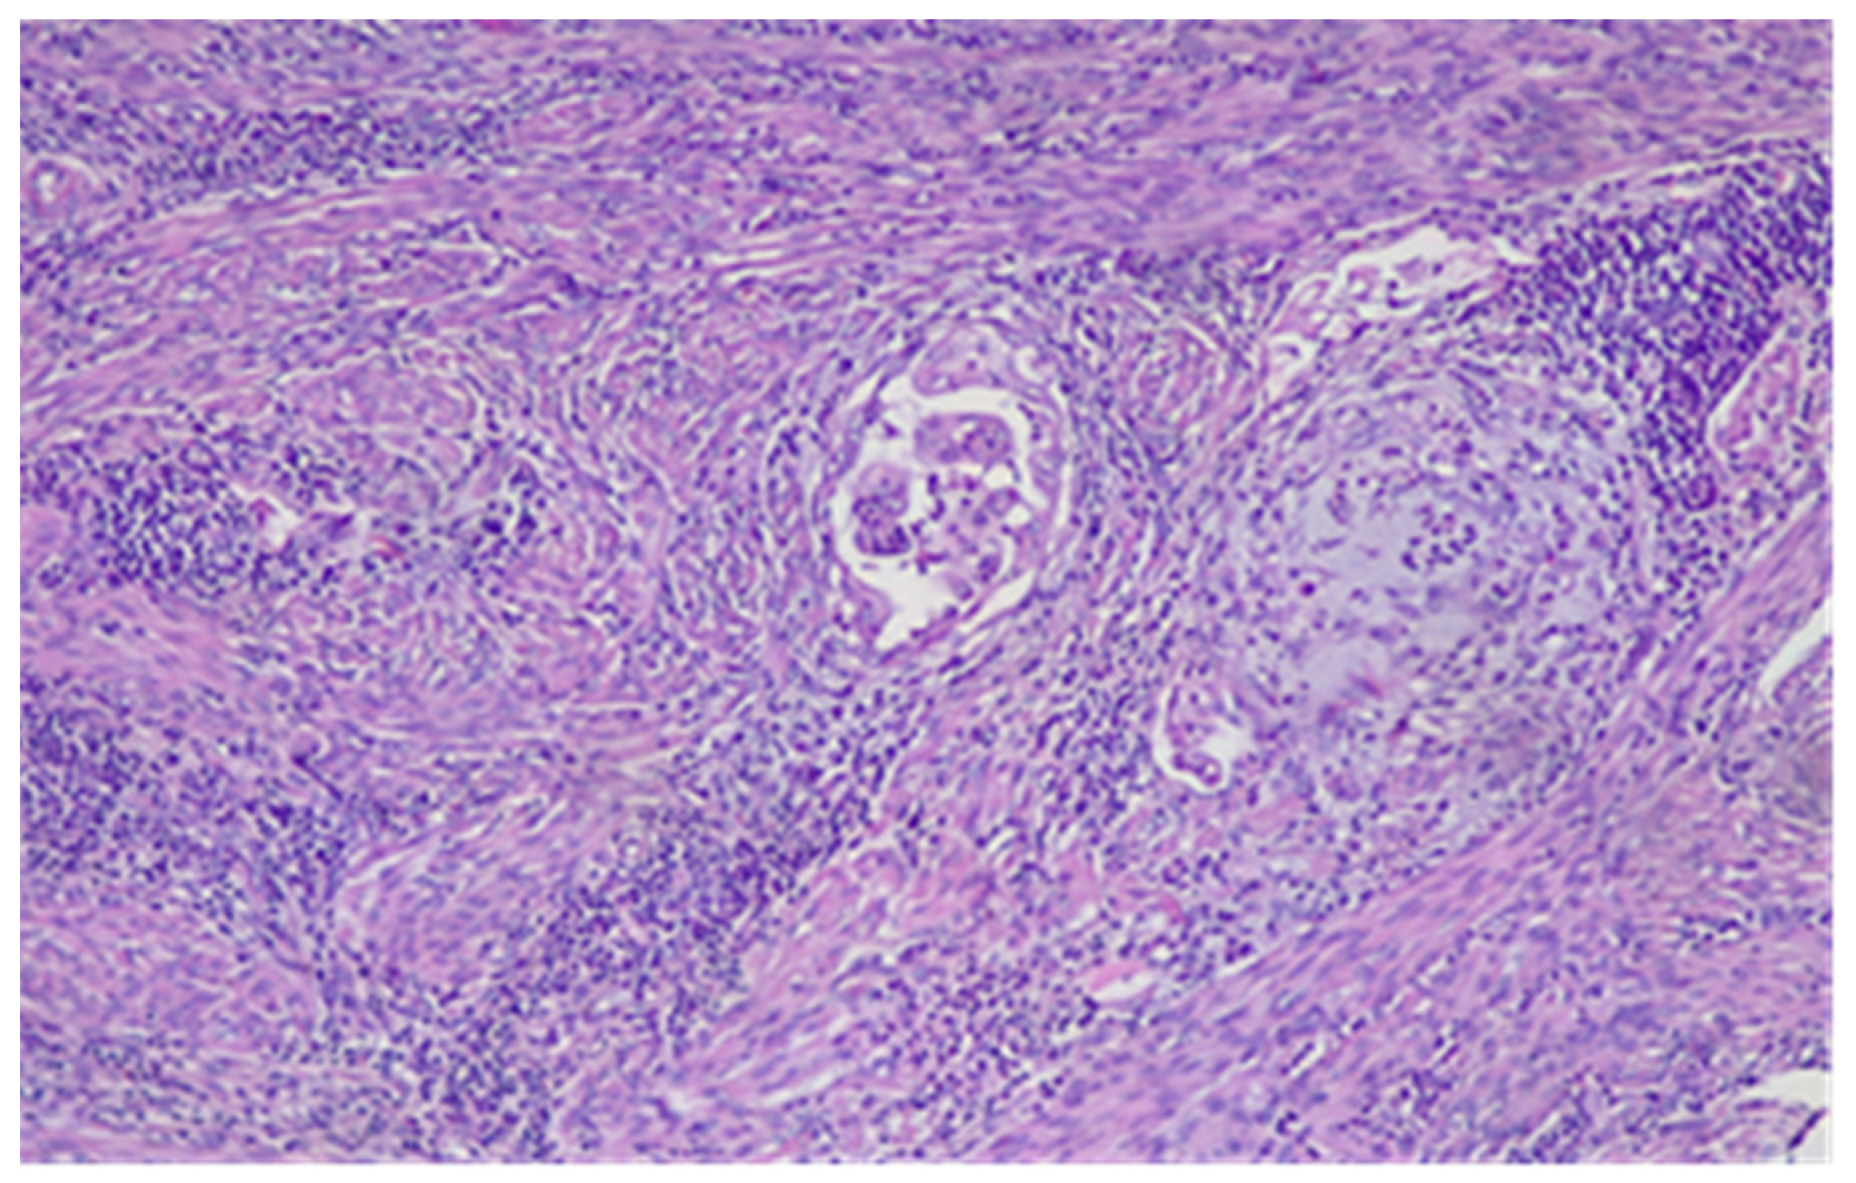

- Microcysts, lined with cells with abundant eosinophilic cytoplasm and vaguely squamoid appearance, or with flattened cells. Lumens often contain neutrophils and occasionally eosinophils.

- Elongated structures lined with the same types of cells and containing the same inflammatory cells in their lumens.

- Clusters of detached cells or individual cells lying in edematous or myxoid tissue.